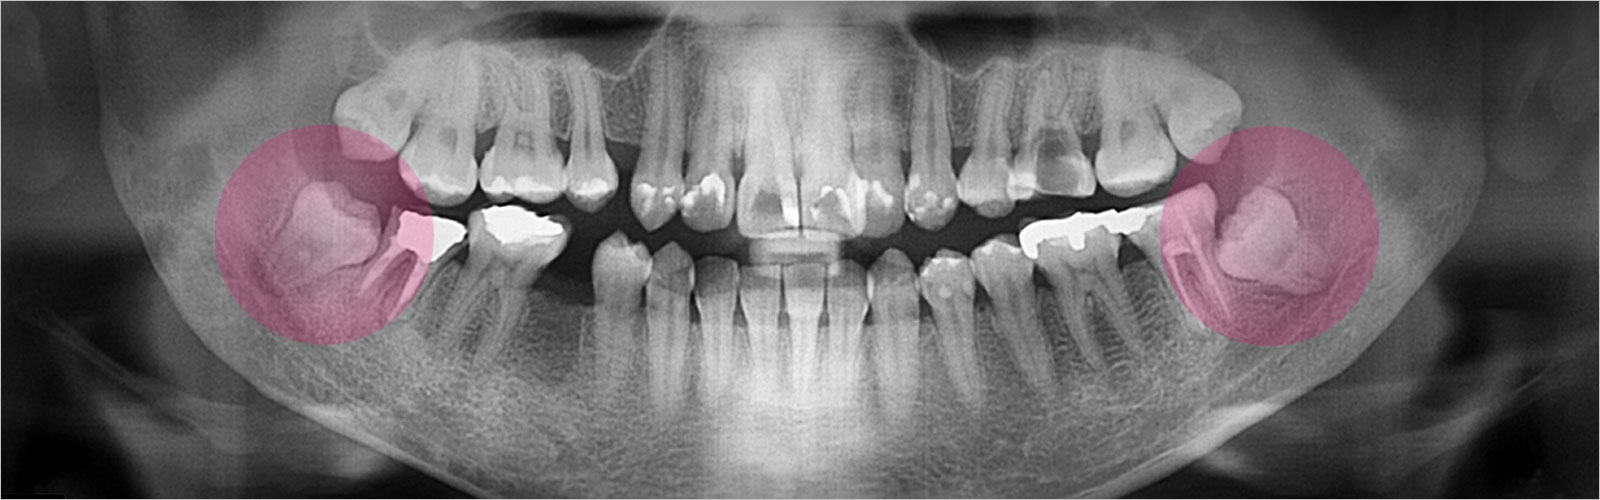

그랜드 치과의 사랑니 클리닉은 정밀한 치과용 CT를 통해 사랑니의 다양한 양상을 정확하게 진단하고 그동안 축적한 임상경험과 노하우를 바탕으로 대학병원에 가지 않고, 또 대학병원처럼 오래 기다릴 필요없이 빠른 시일 안에 사랑니를 안전하게 발치할 수 있습니다.